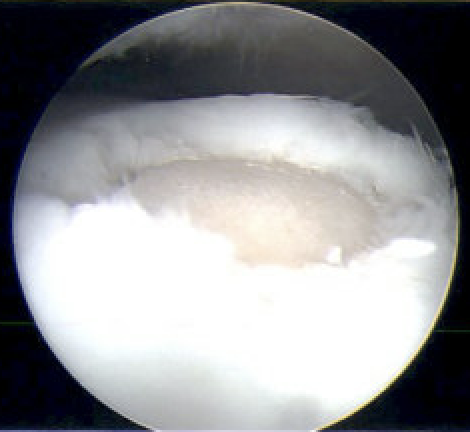

Microfracture

Indications

Chondral lesion < 1 cm diameter

Technique

Arthroscopy techniques microfracture talus